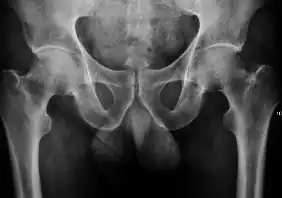

X-ray of infants should be obtained with the pelvis in neutral position with the lower limbs held in neutral rotation and slight flexion.

- Hip dysplasia

Despite the widespread of ultrasound, pelvis X-ray is still frequently used to diagnose and/or monitor hip dysplasia or for assessing other congenital conditions or bone tumors.[1]

The most useful lines and angles that can be drawn in the pediatric pelvis assessing DDH are as follows:[1]

![Figure 2A. Normal hip.[1]](./_assets_/X-ray_of_measurements_on_a_normal_hip.jpg)

![Figure 2B. Hip dysplasia.[1]](./_assets_/X-ray_of_measurements_in_hip_dysplasia.jpg)